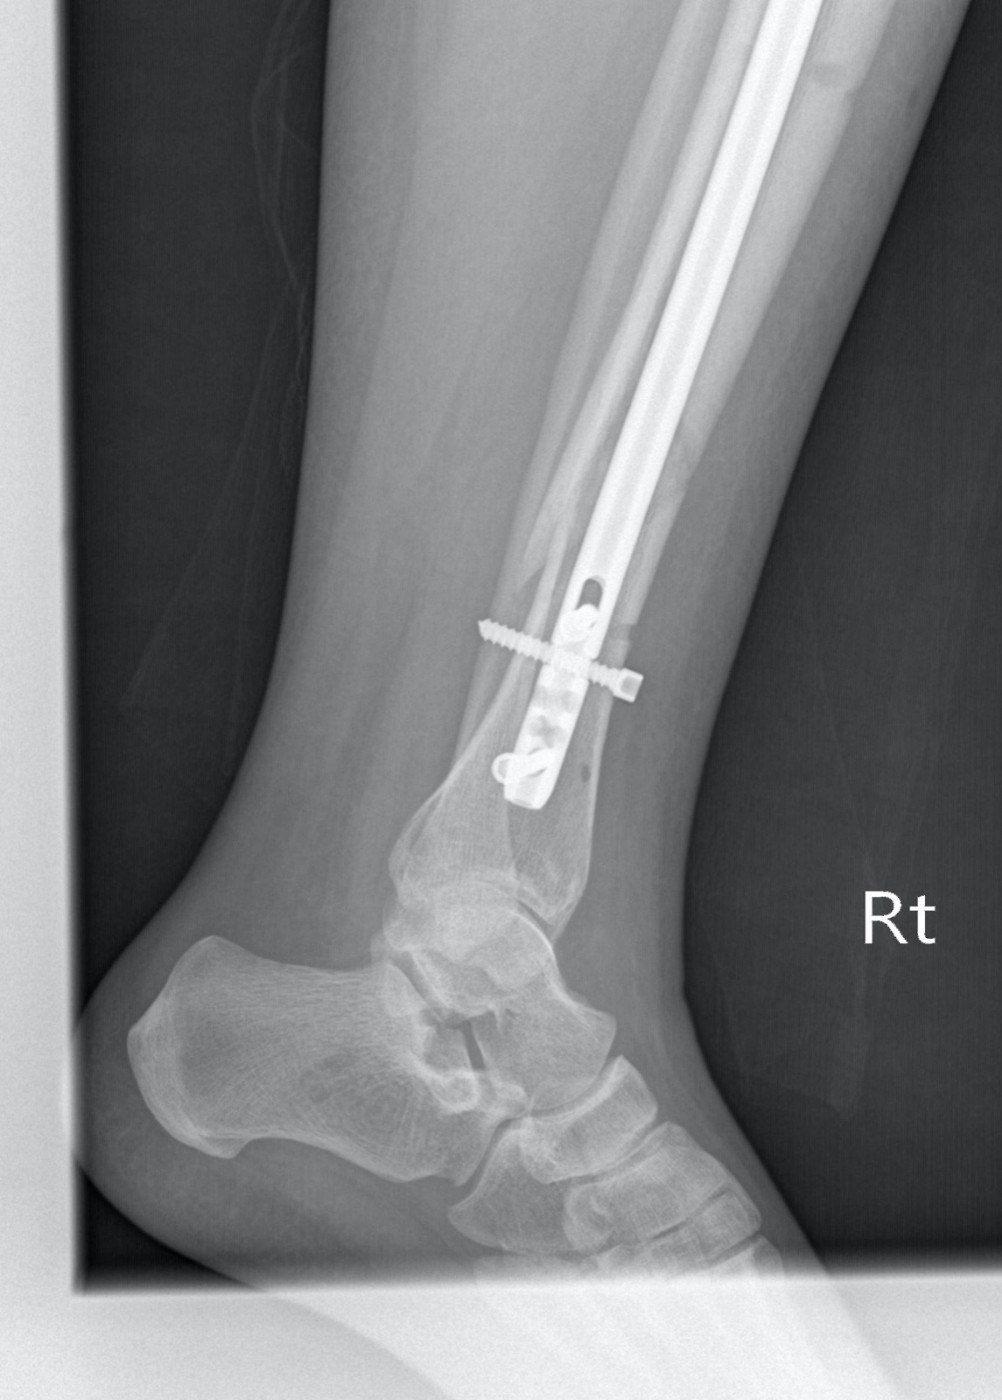

Перелом внутренней лодыжки у ребенка